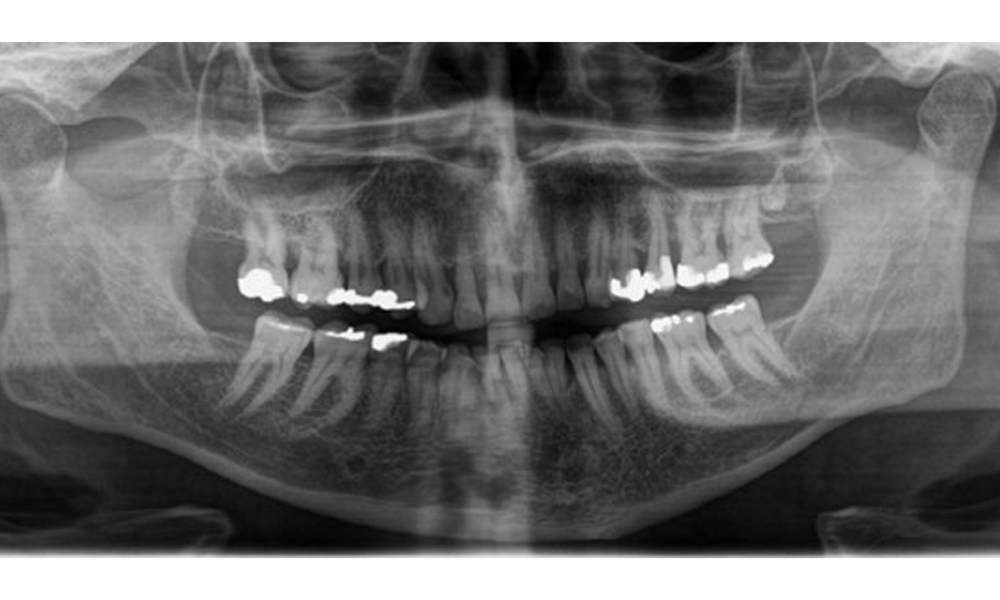

Рентгенологични резултати

Налице е пълно съзъбие на възрастен човек с генерализирана костна загуба между 20-50% и множество зони на вертикална костна загуба. Рентгенологичното изследване не разкрива видими кариозни лезии. (Фиг. 7)